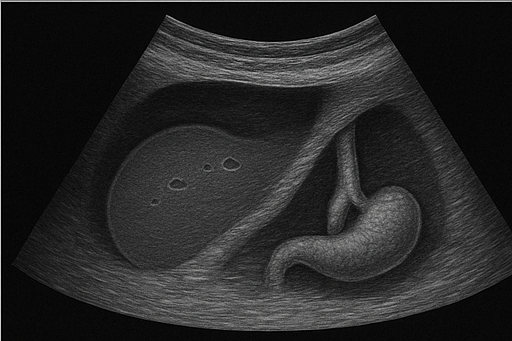

복부 초음파는 우리 몸속의 장기들을 들여다보는 '마법의 창'과도 같은 검사입니다. 간, 담낭, 췌장, 신장 등 복부에 위치한 주요 장기들의 상태를 실시간으로 확인할 수 있어요. 특히 통증 없이 간편하게 진행되기 때문에 많은 분들이 건강검진이나 특정 증상이 있을 때 이 검사를 받습니다.

초음파 검사는 '소리'를 이용한 검사입니다. 사람이 들을 수 없는 고주파의 음파를 몸에 보내면, 이 음파가 장기나 조직에 부딪혀 반사되어 돌아옵니다. 이 반사된 음파를 기계가 받아들여 영상으로 변환시키는 것이죠. 이렇게 생성된 영상은 실시간으로 모니터에 나타나며, 의사는 이를 통해 장기의 상태를 평가합니다.

복부 초음파는 복부에 위치한 여러 장기의 상태를 확인하는 데 사용됩니다. 각 장기별로 어떤 질환을 확인할 수 있는지 살펴보겠습니다.

간

- 지방간: 간에 지방이 과도하게 축적된 상태로, 초음파에서 간의 밝기가 증가하여 확인할 수 있습니다.

- 간염: 간에 염증이 생긴 상태로, 간의 크기 변화나 조직의 불균일한 모습을 통해 감지할 수 있습니다.

- 간경변: 만성 간질환으로 인해 간이 딱딱해지고 울퉁불퉁해지는 상태를 초음파로 확인할 수 있습니다.

- 간암: 간에 발생하는 종양을 초음파로 발견할 수 있으며, 추가 검사를 통해 정확한 진단이 필요합니다.

담낭 및 담관

- 담석: 담낭이나 담관에 생긴 돌로, 초음파에서 밝은 음영과 그림자로 나타납니다.

- 담낭염: 담낭에 염증이 생긴 상태로, 담낭 벽이 두꺼워지고 통증이 동반될 수 있습니다.

- 담낭 용종: 담낭 내부에 생긴 작은 돌출물로, 대부분 양성이지만 크기에 따라 추적 관찰이 필요합니다.

- 담도암: 담관에 발생하는 암으로, 담관의 확장이나 벽의 비정상적인 두꺼움으로 의심할 수 있습니다.